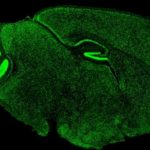

” La componente più importante del circuito di ricompensa del cervello”, ha detto Malenka, ” è un tratto nervoso che corre da una struttura profonda nel cervello chiamata area tegmentale ventrale ad una struttura chiamata nucleo accumbens. La zona tegmentale ventrale ospita un gruppo di cellule nervose o neuroni, le cui proiezioni al nucleo accumbens secernono una sostanza chiamata dopamina, alterando l’attività neuronale in questa regione. La liberazione della dopamina nel nucleo accumbens può produrre un’ondata di piacere che dice al cervello che l’evento in corso è utile per la sopravvivenza.

Così Malenka ed i suoi colleghi hanno progettato esperimenti per chiarire il ruolo dell’ossitocina nel comportamento sociale. Essi hanno confermato il ruolo nella socialità del tratto che corre dal nucleo paraventricolare all’area tegmentale ventrale, tratto in cui si produce l’ossitocina. I ricercatori hanno dimostrato che la disgregazione dell’ attività di questa area ha inibito la socialità, ma non ha compromesso il movimento del topo o il suo “desiderio di assunzione” delle droghe come la cocaina.

I ricercatori hanno dimostrato che l’ossitocina secreta nell’area tegmentale ventrale da parte dei neuroni originari del nucleo paraventricolare, favorisce la sociocialità legandosi ai recettori dei neuroni che escono dal tratto che va dalla zona tegmentale ventrale al nucleo accumbens.